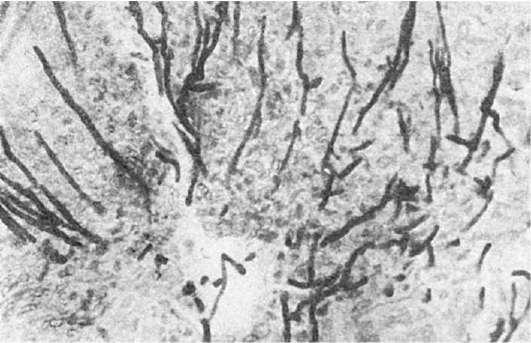

При кандидозе пищеварительного тракта поражаются все его отделы. Кандидоз пищевода наиболее часто встречается в раннем детском возрасте. На слизистой оболочке пищевода образуются пленки, которые в ряде случаев почти полностью закрывают его просвет. Поражения желудка встречаются сравнительно редко. Однако грибы могут обнаруживаться при язвенной болезни в дне язвы и быть источником генерализованного кандидоза. Поражение кишечника (рис. 287) представлено язвами и псевдомембранозными наложениями.

Рис.

287. Кандидоз. Грибковый колит. Врастание гриба Candida в ткань фолликула толстой кишки